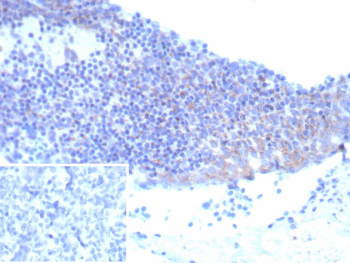

Immunohistochemistry analysis of CD25 / IL2RA antibody (clone IL2RA/9378R) in human tonsil. Formalin-fixed, paraffin-embedded human tonsil tissue shows membranous and cytoplasmic brown chromogenic staining in scattered lymphoid cells, consistent with IL2RA-positive immune cell populations. Inset shows a PBS-only negative control processed without primary antibody, demonstrating minimal non-specific background staining.